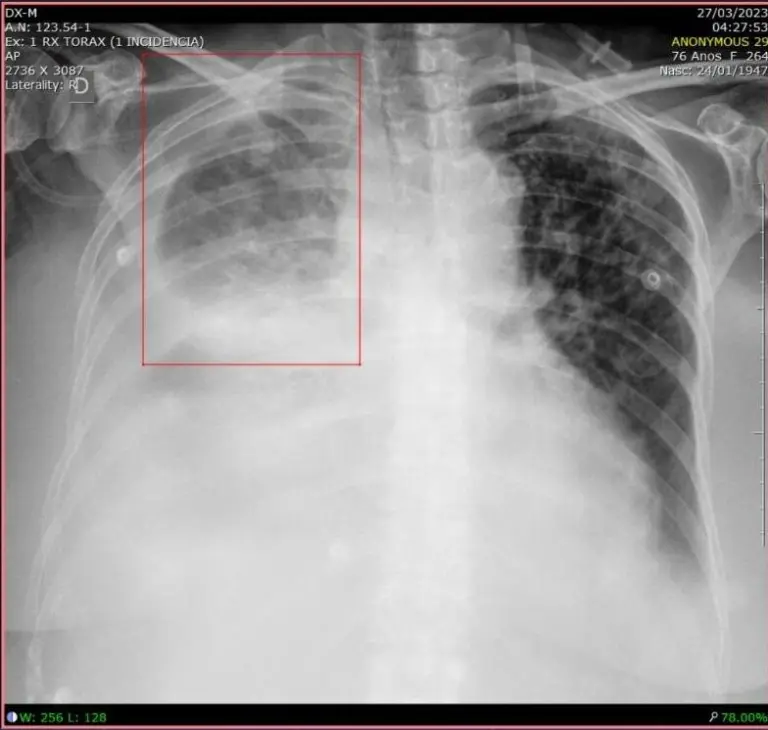

AI for Pulmonary X-Rays

Pneumonia is a lung infection responsible for over 600,000 hospitalizations annually in Brazil’s Unified Pneumonia is a pulmonary infection responsible for more than 600 thousand hospitalizations per year in the Brazilian Sistema Único de Saúde (SUS).

Diagnosing pneumonia on a chest X-ray involves trained specialists and cross-referencing information from clinical history, vital signs, and laboratory tests.

To help with this challenge, machine learning algorithms can detect areas of pulmonary opacity (pleural effusion, cardiomegaly, acute pulmonary edema, pulmonary nodules) and mark them in boxes for medical evaluation, specifying the location and size of any detected infection.

This brings productivity for physicians regarding treatment decisions (mild pneumonia versus severe pneumonia, for example) and also feeds the system back as physicians validate or discard the clinical finding indicated by the computer.